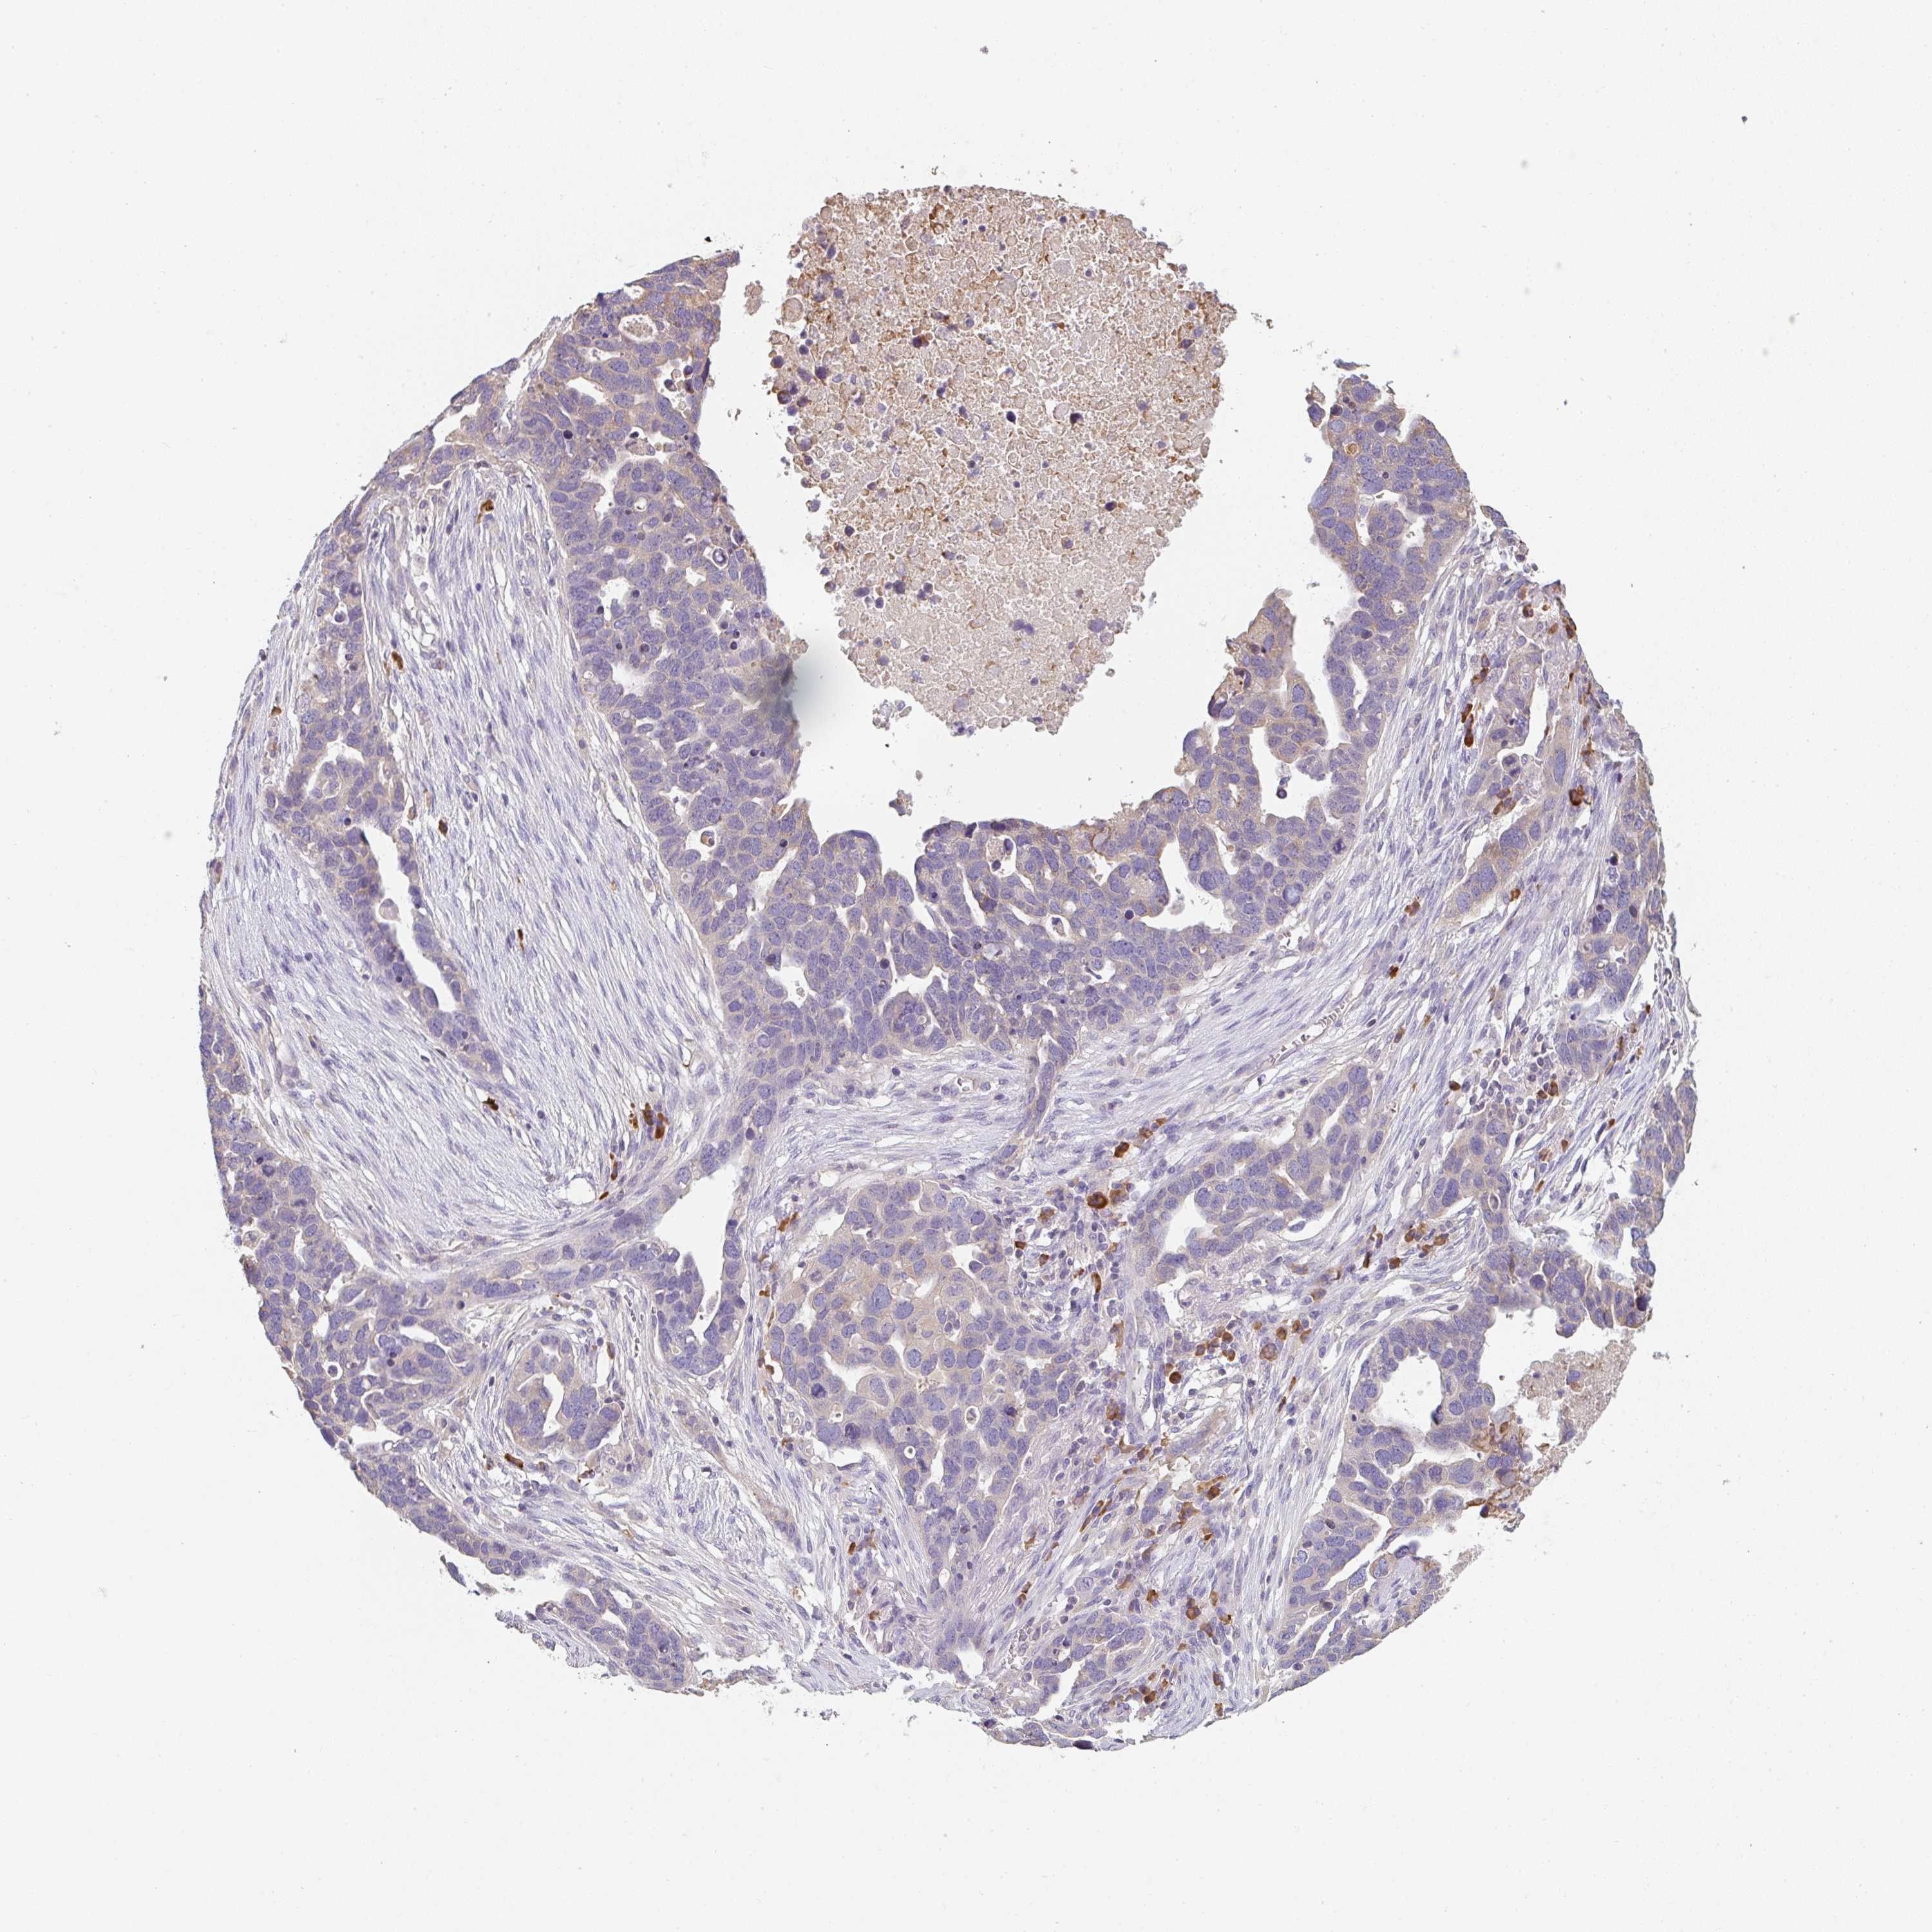

OVARIAN CANCER - Protein expressioni

A mouse-over function shows sample information and annotation data. Click on an image to view it in a full screen mode. Samples can be filtered based on level of antibody staining by selecting one or several of the following categories: high, medium, low and not detected. The assay and annotation is described here.

Note that samples used for immunohistochemistry by the Human Protein Atlas do not correspond to samples in the TCGA dataset.

Antibody stainingi

Antibody staining in the annotated cell types in the current human tissue is reported as not detected, low, medium, or high, based on conventional immunohistochemistry profiling in selected tissues. This score is based on the combination of the staining intensity and fraction of stained cells.

Each image is clickable and will lead to virtual microscopy that enables deeper exploration of all samples and also displays staining intensity scores, fraction scores and subcellular localization as well as patient and tissue information for each sample.

Antibody HPA051010

Staining

High

Medium

Low

Not detected

Intensity

Strong

Moderate

Weak

Negative

Quantity

>75%

75%-25%

<25%

None

Location

Nuclear

Cytoplasmic/membranous

Cytoplasmic/membranous,nuclear

Cystadenocarcinoma, serous, NOS

Carcinoma, endometroid

Cystadenocarcinoma, mucinous, NOS

Carcinoma, NOS